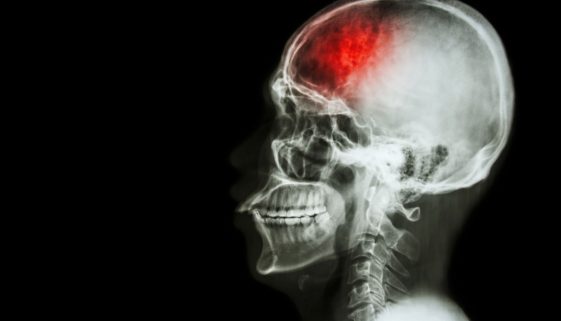

نصائح وتعليمات تثقيفية بخصوص علاج حالات نزيف المخ

يُعتبر نزيف المخ من الحالات الطبية الطارئة التي تتطلب رعاية فورية وعناية مركزة. يُعرف أيضًا بالنزيف الدماغي، ويحدث عند تمزق أوعية دموية داخل المخ، مما يؤدي إلى تجمع الدم. هذا التجمع يزيد من الضغط على أنسجة المخ، ويؤدي إلى تلف الخلايا. في هذه المقالة، سنستعرض النصائح والتعليمات التثقيفية بخصوص علاج […]